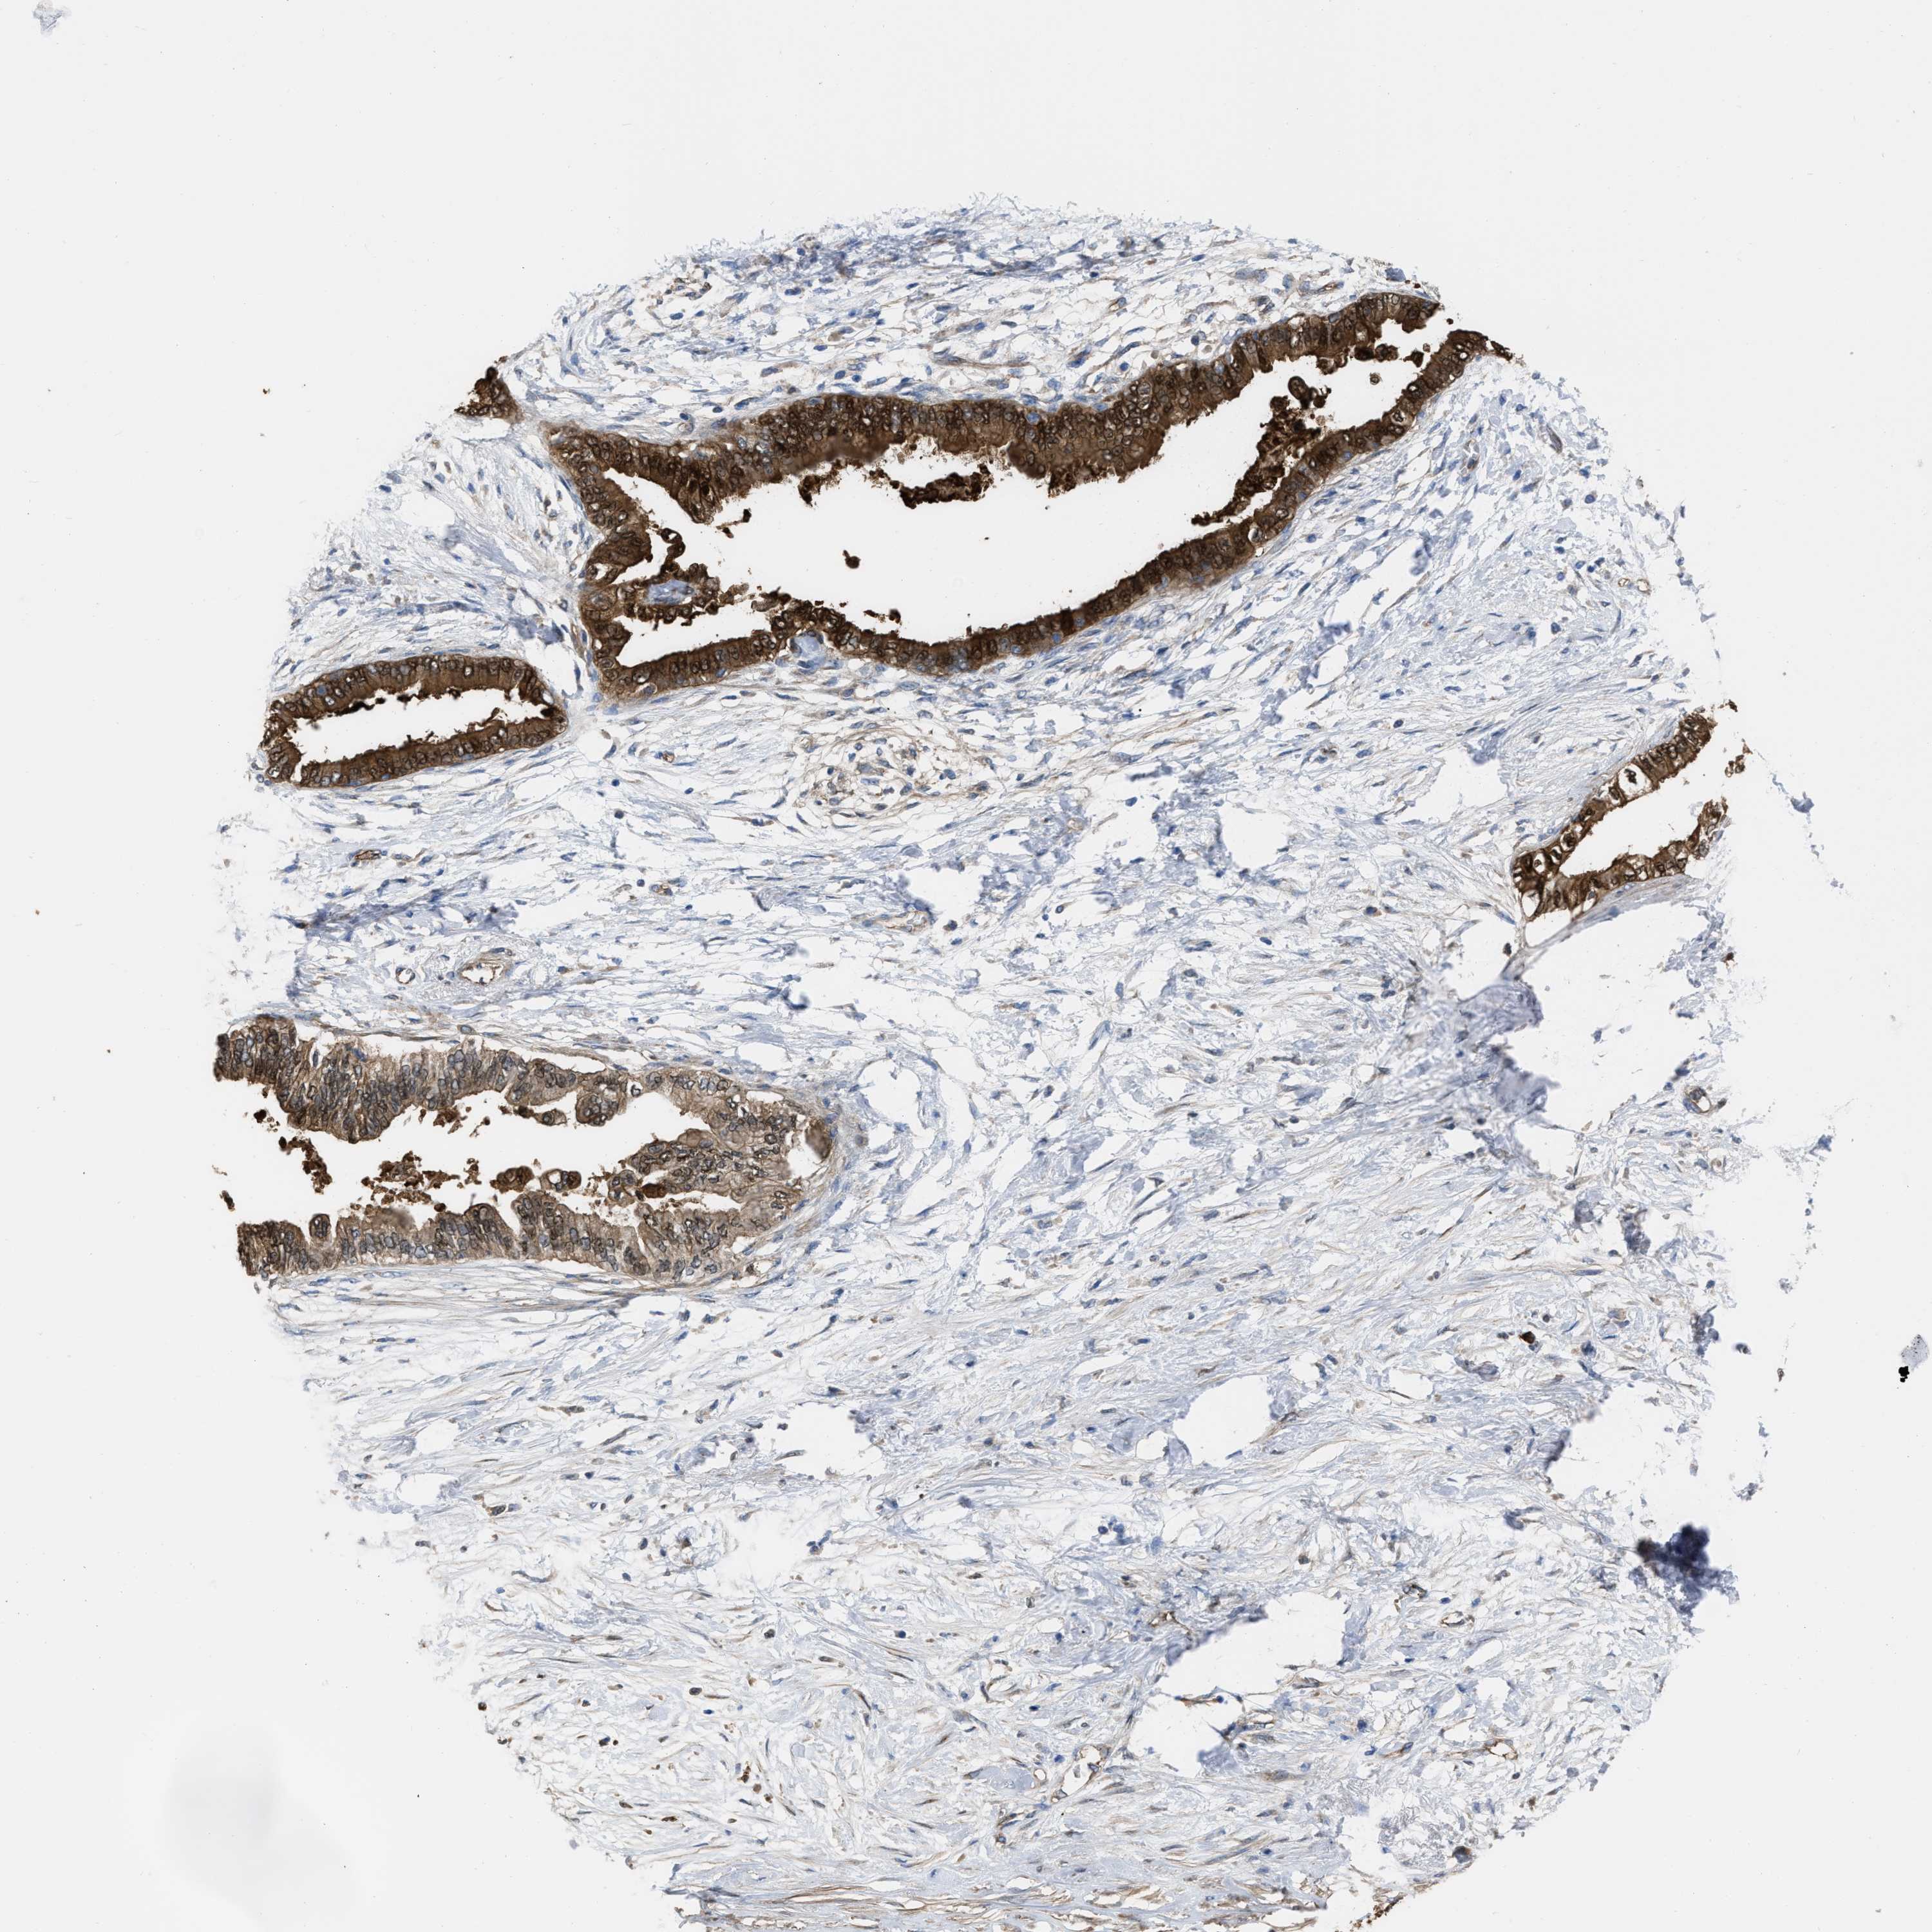

PANCREATIC CANCER - Protein expressioni

A mouse-over function shows sample information and annotation data. Click on an image to view it in a full screen mode. Samples can be filtered based on level of antibody staining by selecting one or several of the following categories: high, medium, low and not detected. The assay and annotation is described here.

Note that samples used for immunohistochemistry by the Human Protein Atlas do not correspond to samples in the TCGA dataset.

Antibody stainingi

Antibody staining in the annotated cell types in the current human tissue is reported as not detected, low, medium, or high, based on conventional immunohistochemistry profiling in selected tissues. This score is based on the combination of the staining intensity and fraction of stained cells.

Each image is clickable and will lead to virtual microscopy that enables deeper exploration of all samples and also displays staining intensity scores, fraction scores and subcellular localization as well as patient and tissue information for each sample.

Antibody HPA003747

Antibody HPA019769

Staining

High

Medium

Low

Not detected

Intensity

Strong

Moderate

Weak

Negative

Quantity

>75%

75%-25%

<25%

None

Location

Nuclear

Cytoplasmic/membranous

Cytoplasmic/membranous,nuclear

Adenocarcinoma, NOS

Adenocarcinoma, metastatic, NOS